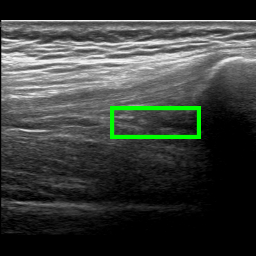

A joint recess can be distended due to three main reasons: it is filled with synovial liquid, it is filled with blood (a condition known as hemarthrosis), and its membrane is thicker due to an inflammation known as synovitis. When the SQR is distended, it appears thicker on the US image. In some cases this can be clearly visible because the joint recess appears as a large dark area. Figure 2 shows three examples of the longitudinal SQR scan. In Figure 2a the SQR is the dark area shown in the green box. In this case the SQR is thin, hence it is not distended. Vice versa, in Figure 2b the SQR is much thicker, indicating that it is distended. While Figure 2a and 2b show two characteristic examples with stark differences, there are borderline cases where the SQR appears slightly enlarged but it is not distended (see Figure 2c) or it is very slightly distended.

Refer to caption

(a) Non-distended SQR

(b) Distended SQR

(c) Borderline Non-distended SQR

Figure 2: Examples of longitudinal SQR scans